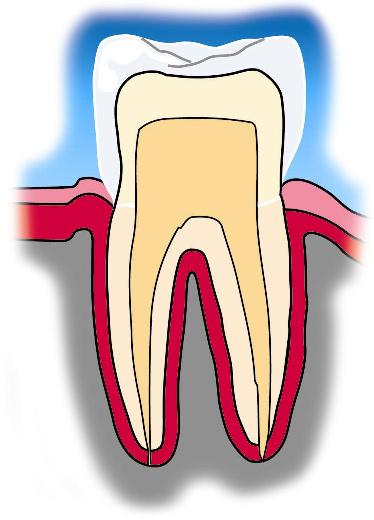

Schwellungen des Zahnfleisches, Rötungen und Blutungen sind Alarmzeichen für eine Zahnfleischentzündung. Aus ihr entwickelt sich häufig eine Parodontitis. Dies ist die Entzündung des Zahnhalteapparates. Untersuchungen zeigen, dass bis zu 80% der Bevölkerung daran leiden. Nach dem 40. Lebensjahr gehen dadurch mehr Zähne verloren als durch Karies.

Warum krankes Zahnfleisch behandelt werden sollte

Spezielle Bakterien, genetische Veranlagung und mangelnde Mundhygiene beeinflussen den Krankheitsverlauf. Bakterien im Mund kleben sich in Biofilmenauf Zahnoberflächen und Zahnfleisch fest. Diese Beläge und Bakterien breitensich entlang der Zähne in die Tiefe aus. Es entstehen immer tiefere Zahnfleisch-taschen und der Kieferknochen wird angegriffen. Am Ende lockern sich die Zähne und fallen aus.